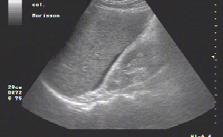

• identificarea sacului pericardic, a colecțiilor pericardice și impactul de tip tamponadă (fig.1) cu risc de activitate electrică fără puls – necesitatea pericardiocentezei într-un serviciu de cardiologie-chirurgie cardiovasculară;

Fig.1. Secțiune subxifoidiană. Colecție pericardică. Cavități cardiace drepte colabate. Ventricul stâng cavitate redusă

Fig.4. Secțiune intercostală dr. venă cavă inferioară